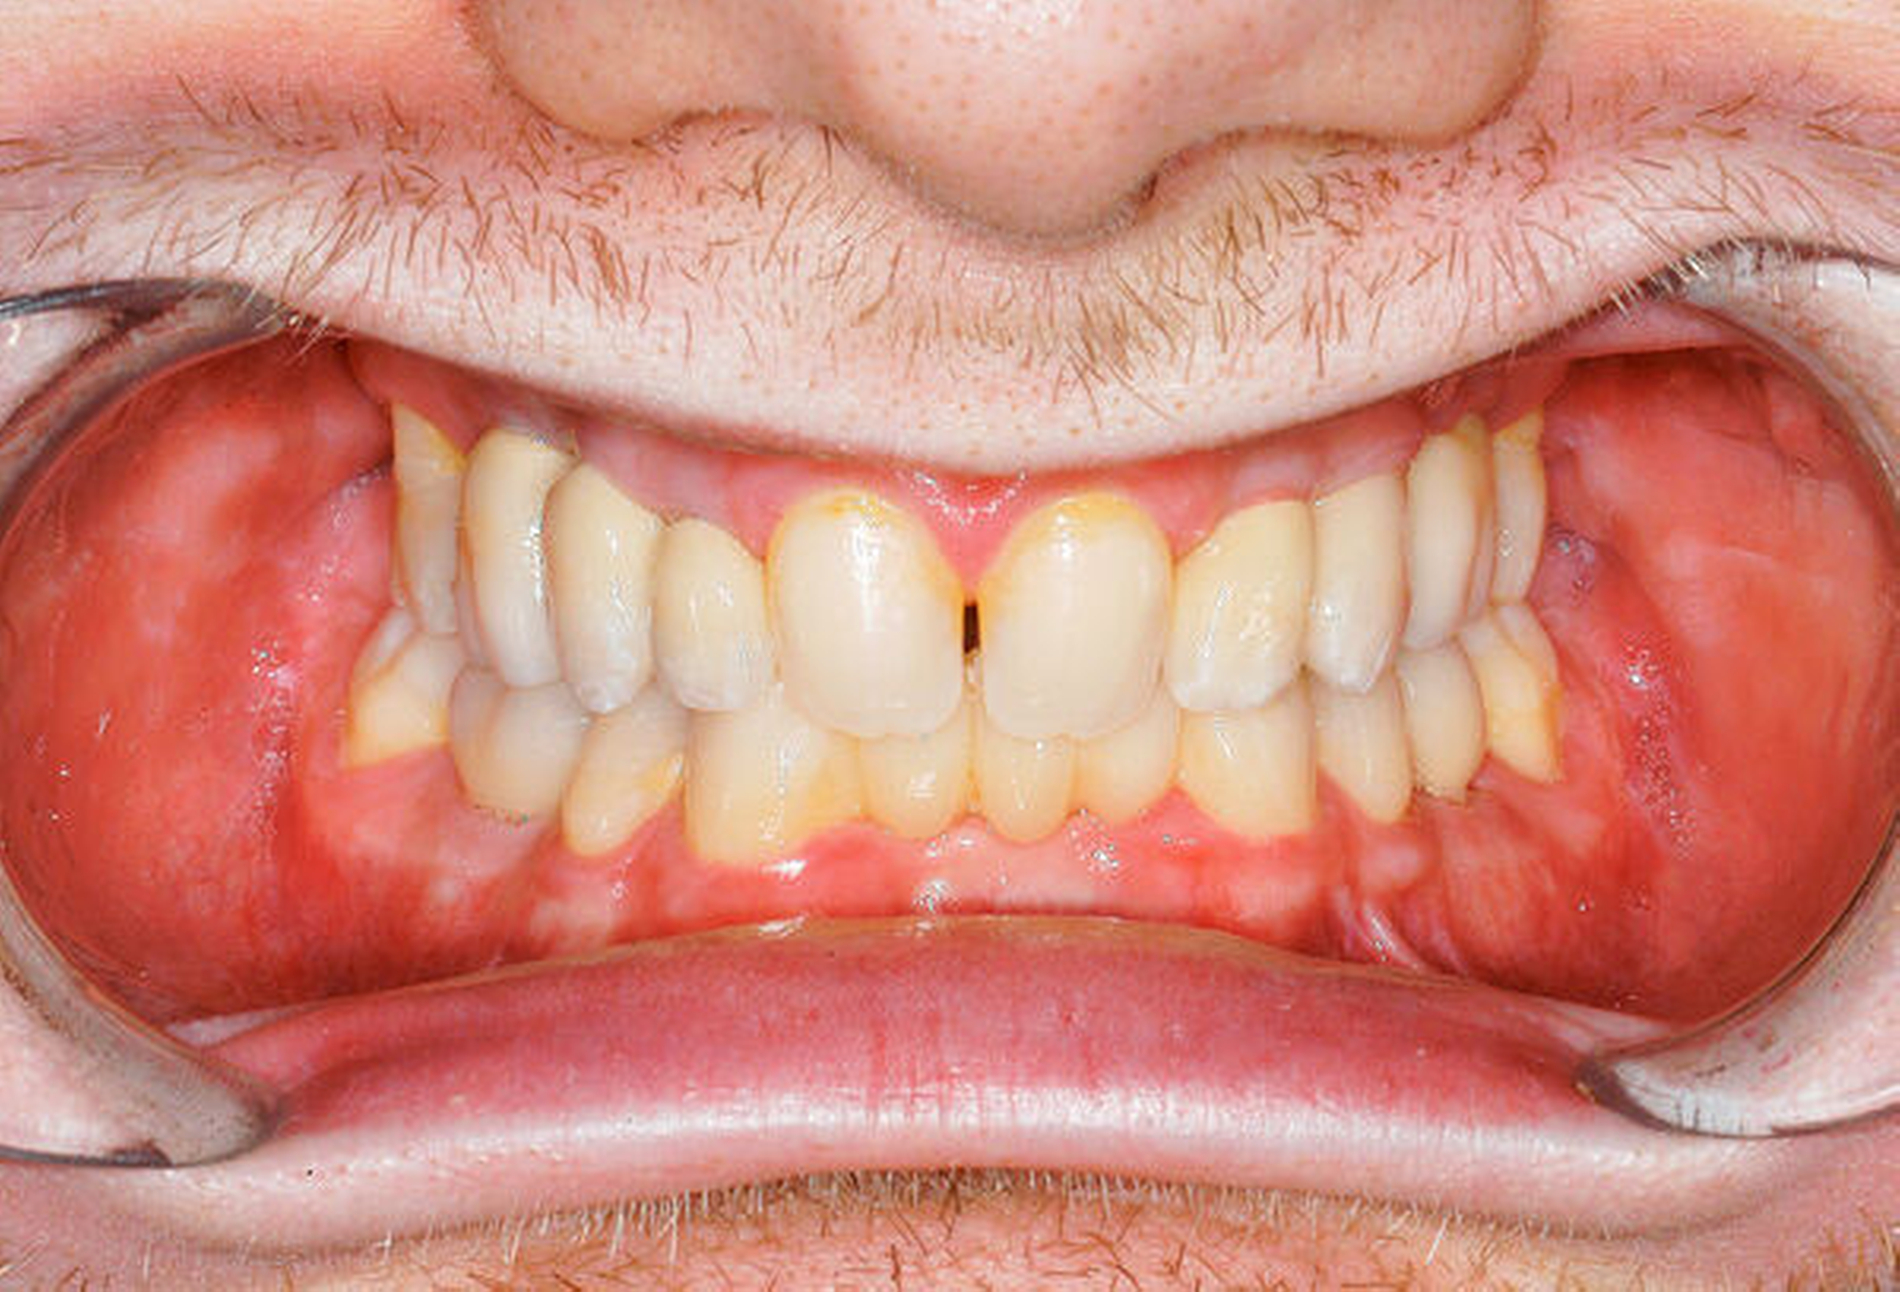

Ein damals 19-Jähriger (Abbildung 1) wurde 2017 in unserer interdisziplinären Implantatsprechstunde zur Beratung bezüglich seiner Zahnnichtanlagen vorstellig. Äußerlich zeigte der Patient keine klassischen Merkmale einer ektodermalen Dysplasie wie beispielsweise eine Hypotrichose, er berichtete jedoch, dass er tendenziell wenig schwitze und seine Haut eher trocken und rissig sei.

Beim intraoralen Befund imponierten neben multiplen Lücken ein partiell seitlich-offener Biss, eine auffällig konische Form der oberen mittleren Schneidezähne sowie persistierende Milchzähne (Abbildungen 2 bis 4). Zusammen mit der angefertigten Panoramaschichtaufnahme (Abbildung 5) konnte der Verdacht einer ausgeprägten Oligodontie bestätigt werden – insgesamt waren 22 Zähne inklusive der Weisheitszähne nicht angelegt. Auf Grundlage der bestehenden Befunde wurde der Verdacht einer genetischen Ursache der Symptome geäußert und dem Patienten zunächst eine molekulargenetische Abklärung mit der Verdachtsdiagnose „genetisch bedingte Zahnnichtanlagen / ektodermale Dysplasie“ empfohlen. Bei der Sequenzanalyse wurde eine Mutation im WNT10A-Gen nachgewiesen und somit die klinische Verdachtsdiagnose bestätigt.